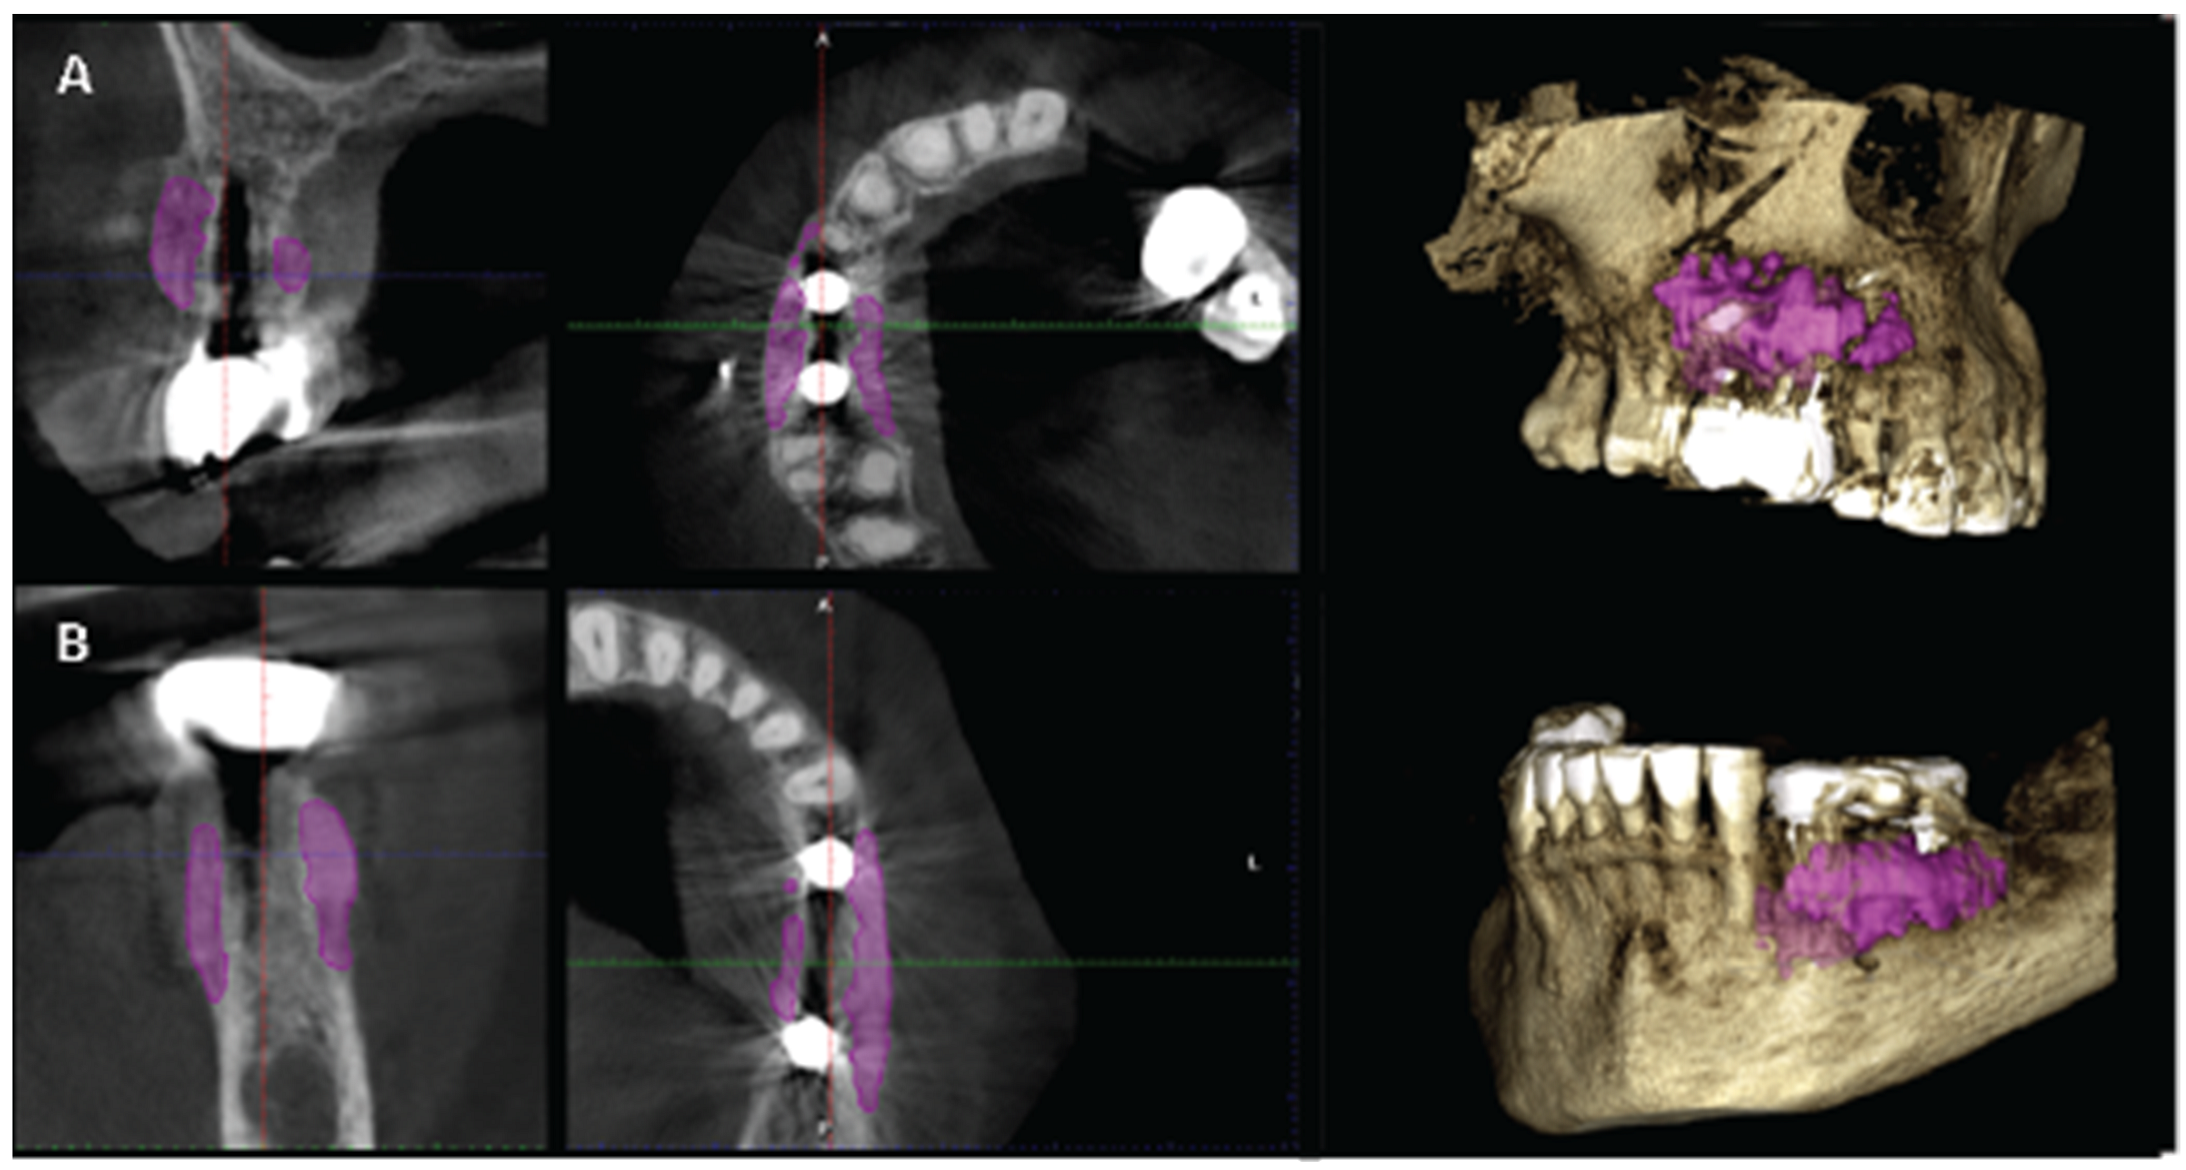

Figure 23. A and B are the T2 images of both patients with manually segmented bone volume gain.

Data Collection

CBCT images were obtained using a CS8100 3D Carestream computed radiography system (Carestream Health, USA), at 0,150mm voxel size and field of view 8x9 cm prior (T1) and 16 weeks (T2) after implant placement. The original files in -DICOM format- were imported into the Romexis software (Planmeca Oy, Tuusula, Finland) for analysis. Both T1 and T2 datasets were superimposed in the software, using a point-based registration and if needed further manual alignment by an experienced oral imaging specialist. 2D measurements were acquired on both registered volumes where a slider tool could help hide and show the second superposed volume. First, measurements on T1 were done, after on T2. The cross-section in the middle of the site on the axial slice, and perpendicular to the alveolar crest was used to measure alveolar widths at 1mm, 3mm and 5mm heights (Figure 21, 22). An approximate Bone volume segmentation of the bone gain was performed on both volumes using a manual segmentation tool to visualize the gain in 3D (see Figure 23).

Significant gains in bone configuration were recorded via CBCT data collection and alveolar width measurements at 3 different levels of the ridge for both T1 and T2 datasets. Values at T2 for the 2 upper maxilla sites ranged from a minimum of 6.45mm to a maximum of 11.10mm with the highest difference T2-T1 recorded at the distal 14 site. Lower site values ranged from a minimum of 4.95 mm to a maximum of 9,75mm with the highest difference T2-T1 at the pontic site 35. Although these values were taken at different levels, if we consider that at least 1 to 2 mm of surrounding hard tissue are necessary for long term stability around dental implants, the current findings show exceptional hard tissue volume around all 4 implant sites. In particular, the value and importance of having a firm attachment and stabilization of the cortical barrier within the healing abutments platforms and over the overgrafted granulated material at a higher level that the one defined from the residual bony ridge at T1, is clearly demonstrated at the cross sectional CBCT images of the pontic site 35. Finally we may appreciate an overall 3D bone volume gain visualization at T2 after bone segmentation volume gains which confirm the results on the cross sectional images. Future studies could also include volumetric analysis on bone gains through STL files.